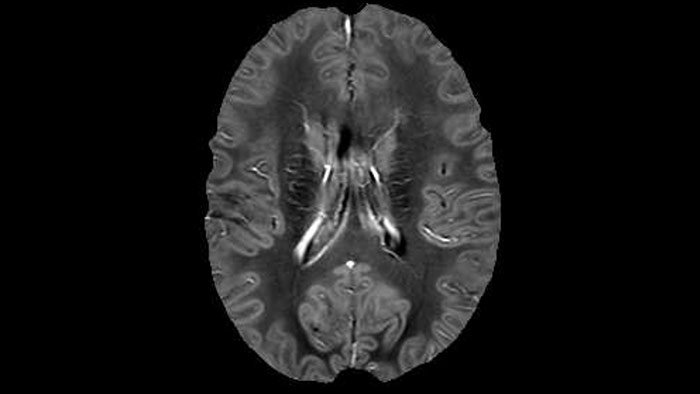

He says the accelerated scanning is achieved via the use of Compressed SENSE and MultiBand SENSE. “We can use Compressed SENSE acceleration factors of about 10 on a 3D FLAIR for instance, which is quite remarkable compared with what we saw with the Achieva. With 3D FLAIR, we can push the spatial resolution to 0.3 cubic mm and it works. Previously, our 3D FLAIR scans lasted about 8 minutes, but now with Elition they are five minutes. The SNR is also visibly better. Our SWI and QSM scans look fantastic. Also, since a lot of neuroimaging is EPI based, using the MultiBand SENSE technique can increase temporal resolution and make it possible to run complicated DTI scans relatively quickly.”

QSM elition Kames algorithm

QSM based on a Compressed SENSE multi-echo SWI.